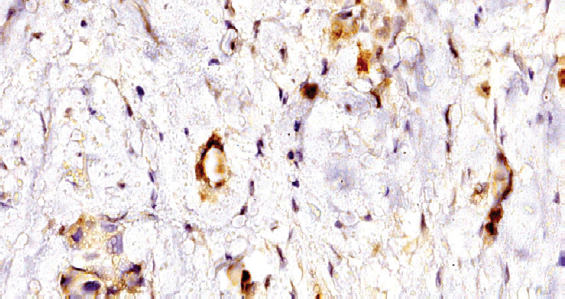

При иммуногистохимическом исследовании материала обнаружена достаточно распространенная экспрессия anti-BLV в различных структурах ткани РМЖ (рис. 1). Продукт реакции определялся в виде зерен и глыбок на поверхности клеточной мембраны, с преобладанием локализации в цитоплазме опухолевых клеток. Выявлена выраженная экспрессия данного вируса на стенке микрососудов (рис. 2). Обратило на себя внимание, что из четырех исследуемых групп экспрессия BLV наблюдалась только в случаях тройного негативного РМЖ (табл. 1).

Рис. 1. Экспрессия антигена вируса лейкоза коров в ткани рака молочной железы, увеличение в 200 раз; иммуногистохимическая окраска

Fig. 1. Expression of cow leukosis virus antigen in breast cancer tissue, zoom in 200; immunohistochemical staining

Рис. 2. Рак молочной железы. Экспрессия антигена вируса лейкоза коров в микрососудах и опухолевых клетках, увеличение в 600 раз; иммуногистохимическая окраска

Fig. 2. Expression of cow leukosis virus antigen in breast cancer tissue, zoom in 600; immunohistochemical staining